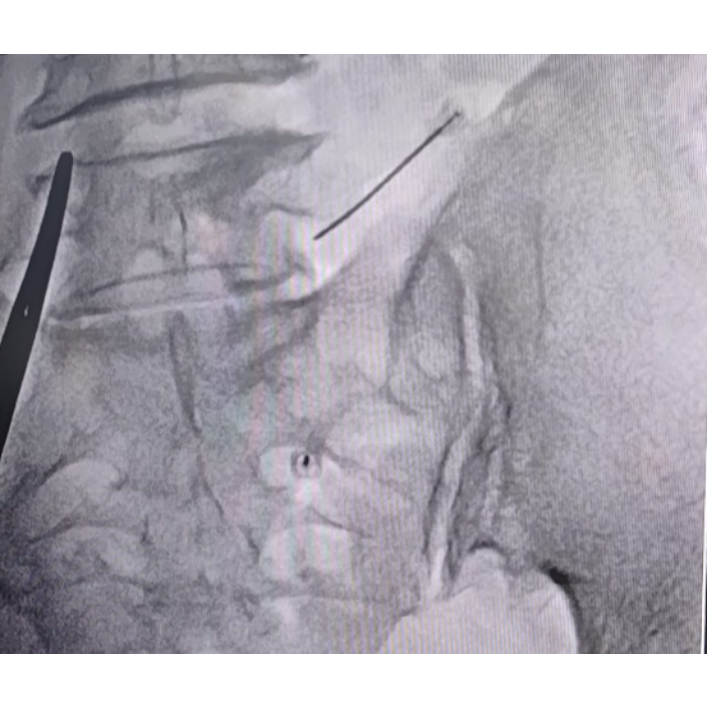

Transforaminal L4,L5,S1 nerve root block !